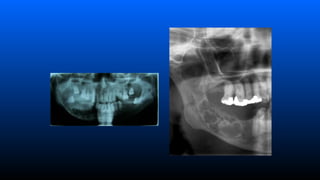

■ Ameloblastoma intra-ósseo

–Aspecto radiográfico

»Lesão radiolucida em forma de bolhas de

sabão multilocular (loculações grandes)

ou favo de mel (loculações pequenas)

associado ou não a um dente incluso;